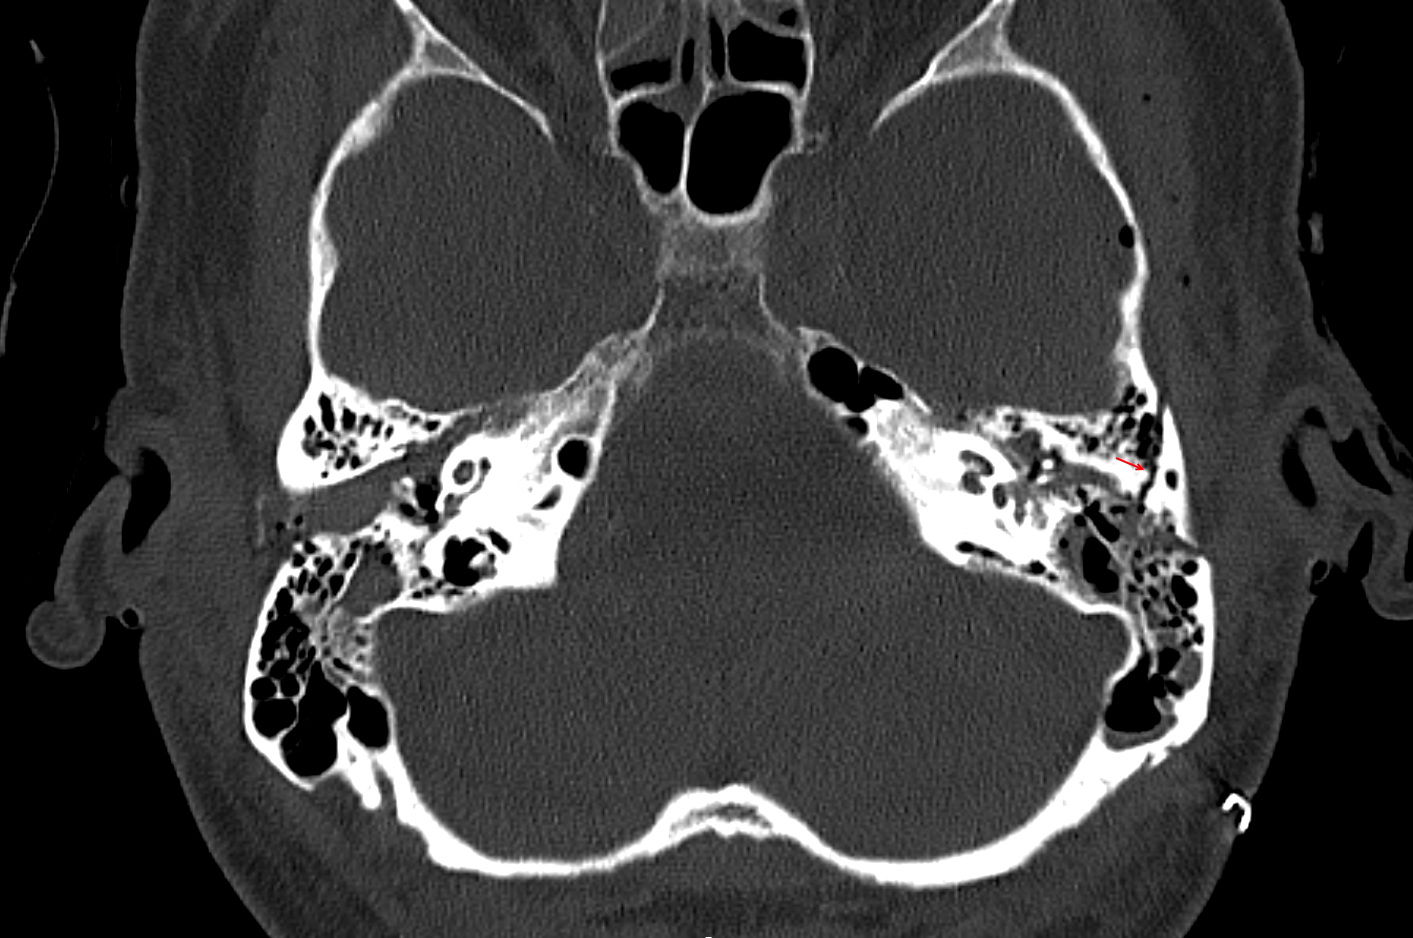

Darstellung einer Felsenbeinquerfraktur (roter Pfeil) in einer axialen CT Bildgebung.

Felsenbeinfraktur CT